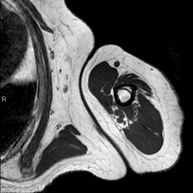

- RM Escrotal (testicular)

Prueba diagnóstica no invasiva que consiste en la obtención de imágenes de alta definición anatómica de la región escrotal mediante el empleo de un campo electromagnético y ondas de radio (con un emisor y un receptor). No utiliza radiación ionizante. En ocasiones se deberá emplear contraste paramagnético (Gadolinio) para completar el estudio. Se utiliza para el estudio detallado de los testículos, para identificar posibles tumores u otras patologías, además de poder visualizar alteraciones de las estructuras adyacentes.